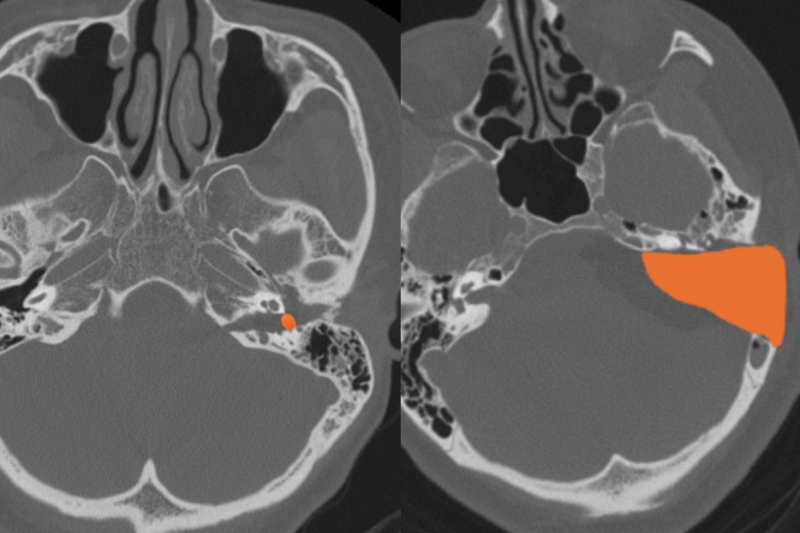

橙色所示听神经瘤切除暴露范围对比(左为持续灌流耳内镜技术,右为传统手术方式)。